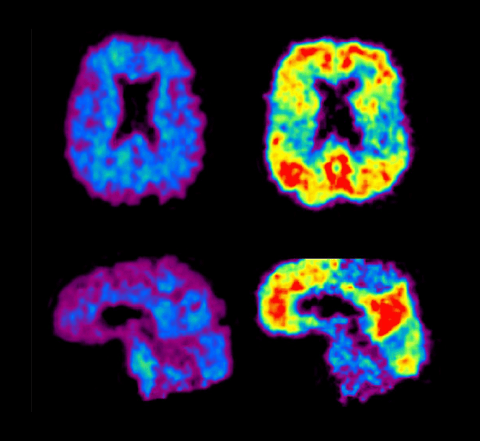

There is increasing interest in using genetic tests and other biomarkers to identify individuals at risk for Alzheimer’s disease (AD). One of these biomarkers is a protein called “amyloid” that can build up and form deposits, called “plaques,” in the brain. Investigators believe that the buildup of amyloid in the brain may play a key role in the later development of AD. Doctors can measure amyloid buildup that may occur many years before cognitive symptoms are present by using a PET scan. However, given the current limitations of predictive testing and AD treatment capabilities, there is much debate about how and whether to disclose such risk information.